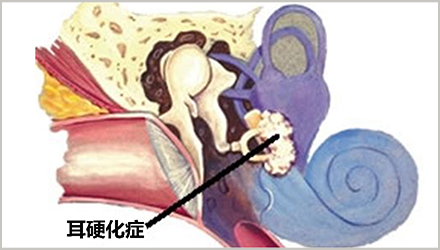

正如动脉粥样硬化会引起动脉硬化一样,耳硬化指的是中耳镫骨底板上出现了异常硬化,从而出现听力下降。

耳硬化目前主要分三种类型:

镫骨硬化症:硬化扩散至镫骨并阻碍其振动,导致传导性听力丧失,这种情况下通常可以通过镫骨切除手术治愈。

耳蜗硬化症:硬化侵入耳蜗,并对连接内耳与大脑的感觉毛细胞或神经通路造成永久性损伤,从而引起感音神经性听力损失,这种情况下镫骨切除术也无效果。

混合型耳硬化症:上述两者兼有,随疾病的发展而出现。